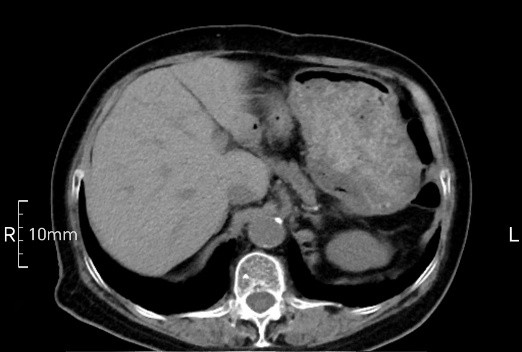

看看下面三幅便知遵醫(yī)囑的重要性。

沒(méi)禁食,胃內(nèi)全是食物,導(dǎo)致胃壁顯示不清。

禁食但檢查前沒(méi)有喝飽,胃未能漲開(kāi),胃壁觀察效果不佳。

完美禁食且喝飽飽,胃壁完美展現(xiàn)。